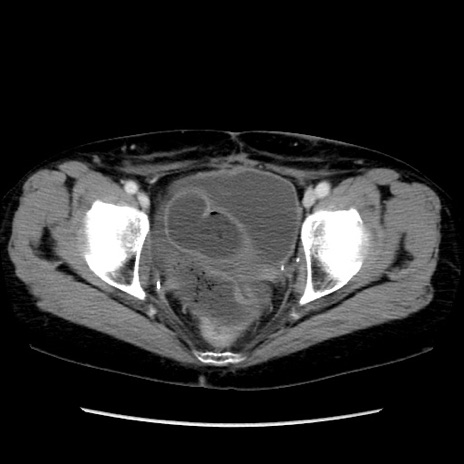

症例32(横断像)

【症例】40歳代 女性

【主訴】上腹部痛、嘔気・嘔吐

【現病歴】約9時間前頃から急に上腹部痛、嘔気、嘔吐が出現。改善しないため救急要請。

【既往歴】子宮頚癌(広汎子宮全摘術、放射線療法)、腸閉塞

【身体所見】腹部:平坦、軟、腸雑音亢進、上腹部を中心に腹部全体に圧痛あり。

【データ】WBC 8400、CRP 0.03